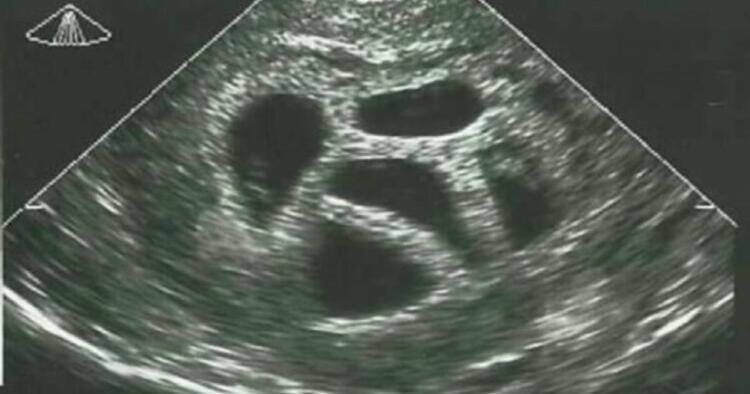

Δεν ήταν έγκυος ούτε σε ένα, ούτε σε δύο αλλά σε πέντε μωρά! Είναι κάτι σπάνιο να συμβεί, αλλά για την Σούζαν έγινε πραγματικότητα. Η 28χρονη τότε μητέρα, συμβουλεύτηκε από τον γιατρό της να ματαιώσει την εγκυμοσύνη, και να κάνει επιλεκτική έκτρωση, αλλά εκείνη αρνήθηκε. Δείτε την φωτογραφία 20 χρόνια μετά!

Αλλά τι είναι μια επιλεκτική έκτρωση; Είναι μια μορφή θεραπευτικής έκτρωσης. Ένα ή περισσότερα έμβρυα αφαιρούνται για να αυξήσουν την πιθανότητα επιβίωσης για τα υπόλοιπα. Η επιλεκτική άμβλωση χωρίς ιατρικούς λόγους που βασίζονται μόνο στο φύλο είναι παράνομη.